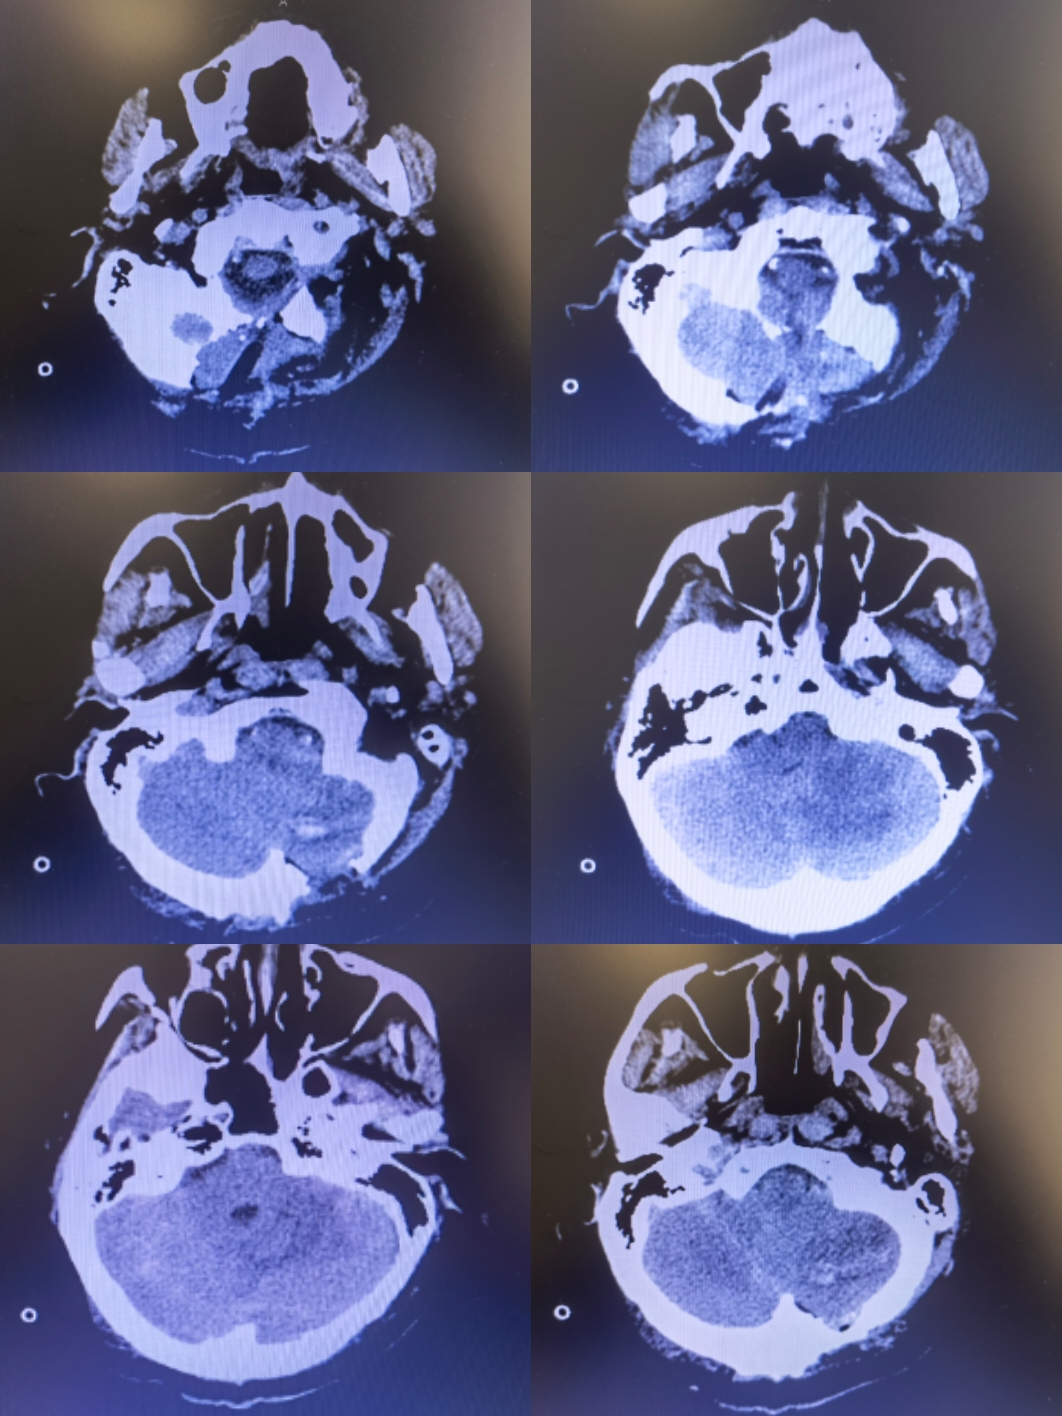

小脑挫裂伤压迫延髓

患者神智嗜睡,给与甘露醇后意识好转,四脑室受压,脑干受压,后期迟发性挫伤和继发性脑肿胀会进一步压迫延髓,给与急诊手术

行脑室外穿刺后行后颅窝去骨瓣减压,术中剪开硬膜后血肿经小脑皮层破出,术后病人意识清楚

思考:小脑挫裂伤后压迫延髓随时可能危及患者生命,早期积极行手术治疗利于患者恢复